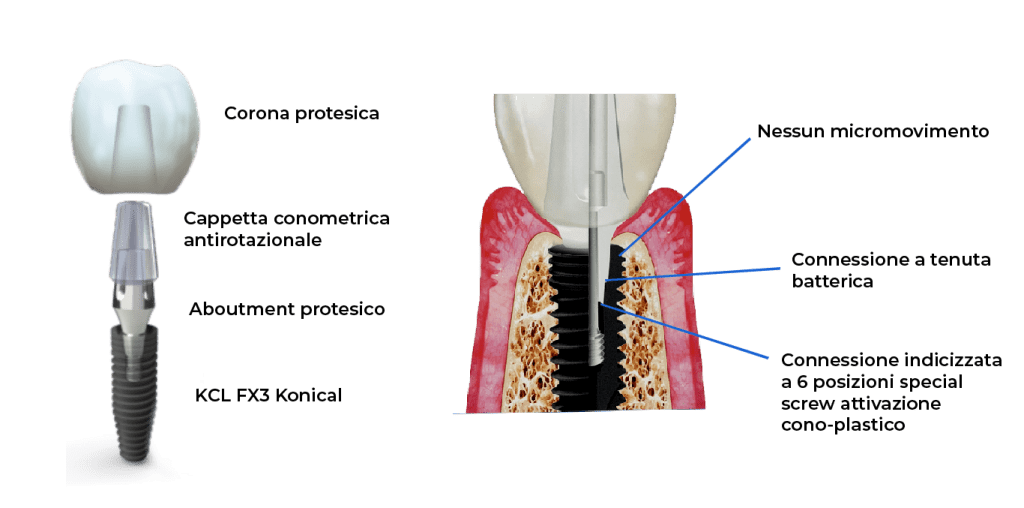

I monconi protesici sono disponibili esclusivamente con una connessione conica non indicizzata, che consente il posizionamento e la parallelizzazione direttamente in studio e, quando consentito, al momento dell’intervento chirurgico.

Per l’odontoiatra questo significa disporre di una procedura che prevede il serraggio monofasico del moncone protesico senza la necessità della sua successiva rimozione, eliminando così fenomeni di infiltrazione batterica che possono dare origine a perimplantiti e/o cunei di riassorbimento osseo che compromettono la sopravvivenza degli impianti nel medio e lungo termine.